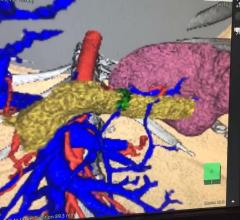

This is an example of a 3-D printed pelvis that had multiple hip fractures and a second printed pelvis is from a post ...